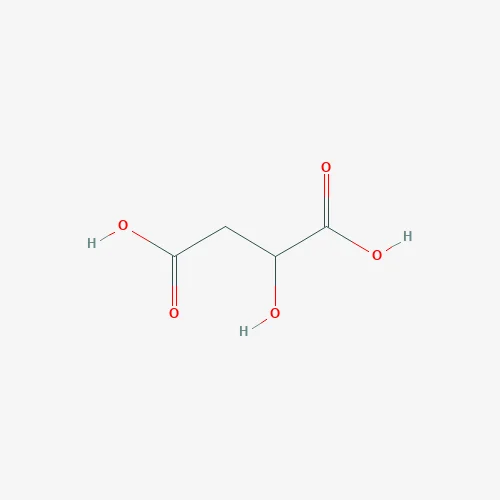

Quick Details Port: Shanghai Port,Tianjin Port Payment Terms: T/T,Western Union,MoneyGram,Bitcoin Supply Ability: 10000.0 Kilogram/Kilograms per Week Other Names: Lignocaine benzyl saccharide Color: White Purity: 99% Grade: Phamaceutical Grade Appearance: WHITE POWER MOQ: 1 Kg CAS No.: 90823-38-4 Type: pharmaceutical intermediates CAS: Denatonium saccharide Product name: Denatonium saccharide EINECS No.: 2020-002-100 MF: C28H33N3O4S Package: Reuquest Application: Pharmaceutical Intermediates Packaging Detail: According to your requirements 1.Product Information Common Name Denatonium saccharide CAS Number 90823-38-4 Molecular Weight 507.644 LogP 5.68580 Exact Mass 507.219177 Molecular Formula C28H33N3O4S PSA . 2.Company Informaiton 3.Packing&Shipping Recommended transportation selections 1.By Express Suitable for sample order or <50kg Fast: 3-10 days High shipping cost 2.By Air Transportation Door to door service Suitable for >50kg Fast: 3-7 days Lower than express cost Airport to airport service 3.By Sea Transportation Professional broker needed Suitable for > 300kg Slow: 7-45 days Port to port service Lowest cost Professional broker needed. 4.Our Service We participate in the exhibition as much as possible to increase the demand for our products, with advanced detection intensity.Ensure the quality of products and offer the best discounts to regular customers.We are at your service 24 hours.Looking forward to your call. 5.Certification […]